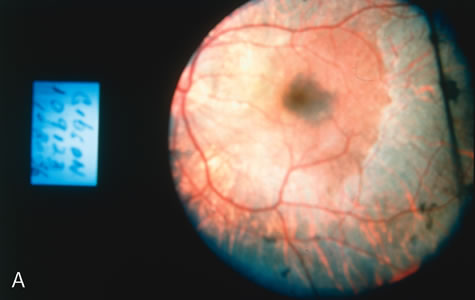

In retinitis pigmentosa (RP), the pigment abnormalities of atrophy, migration, and clumping are made apparent by transmitted hyperfluorescence and blocked hypofluorescence (Fig. 1A). Patients who have very minimal pigmentary alterations (pauci pigmentary RP) or no pigment abnormalities (RP sine pigmento) may show the abnormalities on fluorescien angiography (FA). It is uncommon to see choriocapillaris atrophy except in the late stages. This finding corresponds to the histopathology, which shows that the earliest abnormalities are in the photoreceptors and that the choroid is normal.1